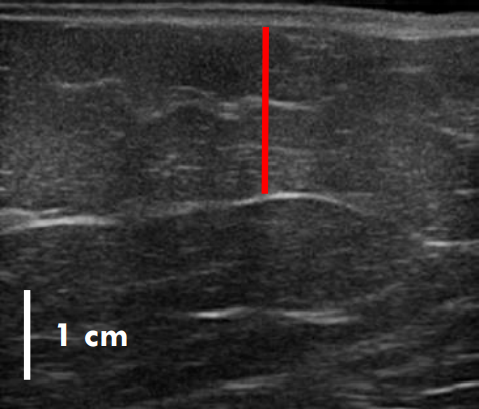

실제 지방이 어느 정도 감소했는지는 초음파 사진을 보면 더욱 뚜렷하게 확인할 수 있는데.

트루스컬프ID 시술 전, 12주 후

초음파를 비교한 사진입니다.

레드 라인이 지방층의 두께입니다.

앞서 보여드린 사례의 경우 시술 전과 비교했을 때 약 36% 정도 지방이 감소한 결과를 볼 수 있는데요.

이 정도의 지방량을 줄이려면 일반적인 운동, 식이요법만으로는 한계가 있지요.